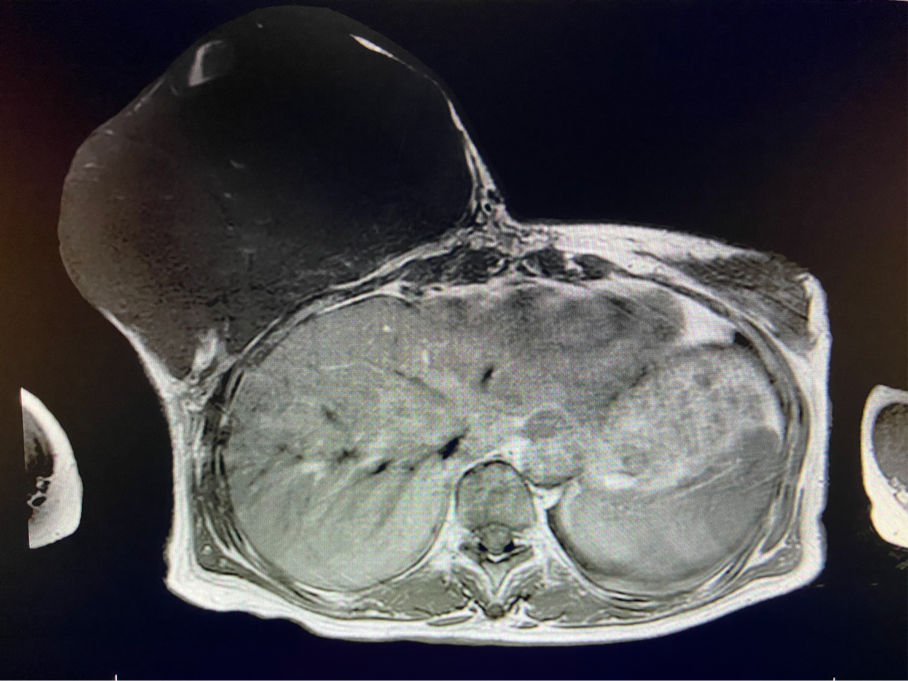

王女士終于可以暢快呼吸、正常走路了,不用再擔心壓在胸前令人窒息的腫瘤和別人異樣的眼光。近日,王女士在西安國際醫(yī)學中心醫(yī)院甲乳外科接受了右乳全乳切除術(shù) 胸壁皮瓣成形術(shù)或植皮術(shù),切除了胸口重達5斤的腫瘤。

6個月前,王女士能感覺到右乳腫物明顯增大至“鴨蛋”一般,而且伴有局部皮膚瘙癢及輕度脹痛,可這次王女士并沒有那么幸運,服藥3個月不僅沒有控制住腫物,脹痛也越發(fā)嚴重,超聲檢查提示:右乳囊實性占位,最大前后徑約10.8cm,右腋窩多發(fā)腫大淋巴結(jié),遂行右乳腫物穿刺活檢術(shù),術(shù)后病理檢查提示:右乳腫物穿刺乳腺組織2條,均可見導管囊性擴張,部分區(qū)域間質(zhì)纖維增生,其中1條內(nèi)導管上皮成普通型增生。輾轉(zhuǎn)當?shù)囟嗉裔t(yī)院藥物治療后,錢沒有少花,但是療效甚微。

2周前,王女士的右乳外下方皮膚破潰,伴大量滲液,還發(fā)出陣陣惡臭。經(jīng)多方打聽,王女士從外地來到西安國際醫(yī)學中心醫(yī)院甲乳外科劉曉敏主任處就診。入院后,迅速完善了一系列相關(guān)術(shù)前檢查:王女士的雙乳外形不對稱,右乳約22?20cm,皮膚水腫明顯并可見靜脈曲張。右乳外下象限皮膚可見局部破潰,創(chuàng)面有3處,共約6?4cm大小,創(chuàng)面呈暗紅色,伴有血性滲出及惡臭,局部皮膚溫度升高。右側(cè)腋窩可觸及腫大淋巴結(jié)。

該患者右乳巨大腫物術(shù)前初步考慮乳腺葉狀腫瘤可能,因腫瘤太大,幾乎遍及整個右側(cè)乳房,為保證“無瘤原則”,術(shù)中切除范圍位置未知,極有可能出現(xiàn)皮瓣缺損。于是,經(jīng)過和整形醫(yī)院郭樹忠院長、整形外科王愛武主任的討論,提供了兩種手術(shù)方式,一是創(chuàng)面修復(fù)(植皮或轉(zhuǎn)移皮瓣修復(fù)創(chuàng)面),二是乳房再造,與患者及家屬溝通后,決定先解決腫物,3年病情不再復(fù)發(fā)后,可以再考慮乳房重建。